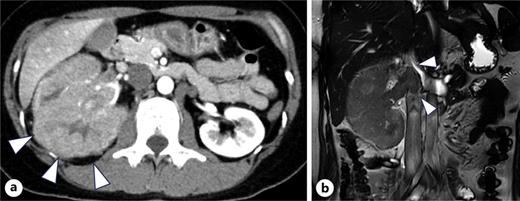

A 34-year-old woman presented with fever and right flank pain. Contrast-enhanced computed tomography (CT) revealed a 116 × 83 mm poorly enhanced solid mass replacing the right kidney, suspicious for RCC and tumor thrombus in the inferior vena cava below the hepatic vein inflow without apparent lymph node or distant metastases (shown in Fig. 1). Brain magnetic resonance imaging (MRI) showed no evidence of brain metastases, and bone scintigraphy revealed no abnormal uptake. The patient’s medical history included depression, and family history was notable for epilepsy in her brother and daughter. Therefore, the patient was diagnosed with non-clear cell RCC at the clinical stage cT3bN0M0. Concurrently, uterine leiomyomas were observed, along with a family history, raising suspicion for HLRCC. Open radical nephrectomy and inferior vena cava tumor thrombectomy were performed. Pathological findings revealed atypical tumor cells with irregular glandular structures and large nucleoli resembling nuclear inclusions. Immunohistochemical analysis showed loss of FH protein in the tumor cells, confirming the diagnosis of FH-deficient RCC, pT3bN0M0, stage III, WHO/ISUP grade 3 (shown in Fig. 2). PD-L1 expression and CD4/CD8-positive lymphocyte infiltration were observed, although most infiltrating lymphocytes were stromal with minimal intratumoral infiltration. Four weeks postoperatively, CT showed no recurrence. Adjuvant immunotherapy with pembrolizumab was initiated owing to the pT3b stage. Genetic counseling was performed with informed consent. Gene sequencing using a hybrid capture method identified a missense variant of FH c.698G>A (p.Arg233His) [NM_000143.4]. According to the ClinVar database (variation ID: 16236), the clinical significance of FH c.698G>A is pathogenic. Combined with her phenotype, we confirm the diagnosis of HLRCC. At week 9 of pembrolizumab therapy, CT revealed bone metastases at Th4, L2, and L3 (shown in Fig. 3). After discussing the available treatment options along with their respective benefits and drawbacks, the patient chose to pursue the most intensive therapy despite potential side effects. These oligometastases were treated with stereotactic body radiotherapy (SBRT) (24 Gy in two fractions). Therefore, systemic therapy with NIVO (240 mg) and cabozantinib (40 mg) was initiated. The patient remained stable disease for 16 months since the recurrence. Genomic testing using the FoundationOne CDx® panel identified the known FH mutation and genetic abnormalities in PIK3R1 and TP53; however, no additional actionable mutations were detected. Mutations in BRCA1/2 have been identified; however, these have been classified as variants of uncertain significance. After undergoing multidisciplinary genetic counseling, the patient consented to genetic testing of her 9-year-old daughter, which revealed the same FH gene mutation. Consequently, annual MRI screening of pediatric patients was initiated.